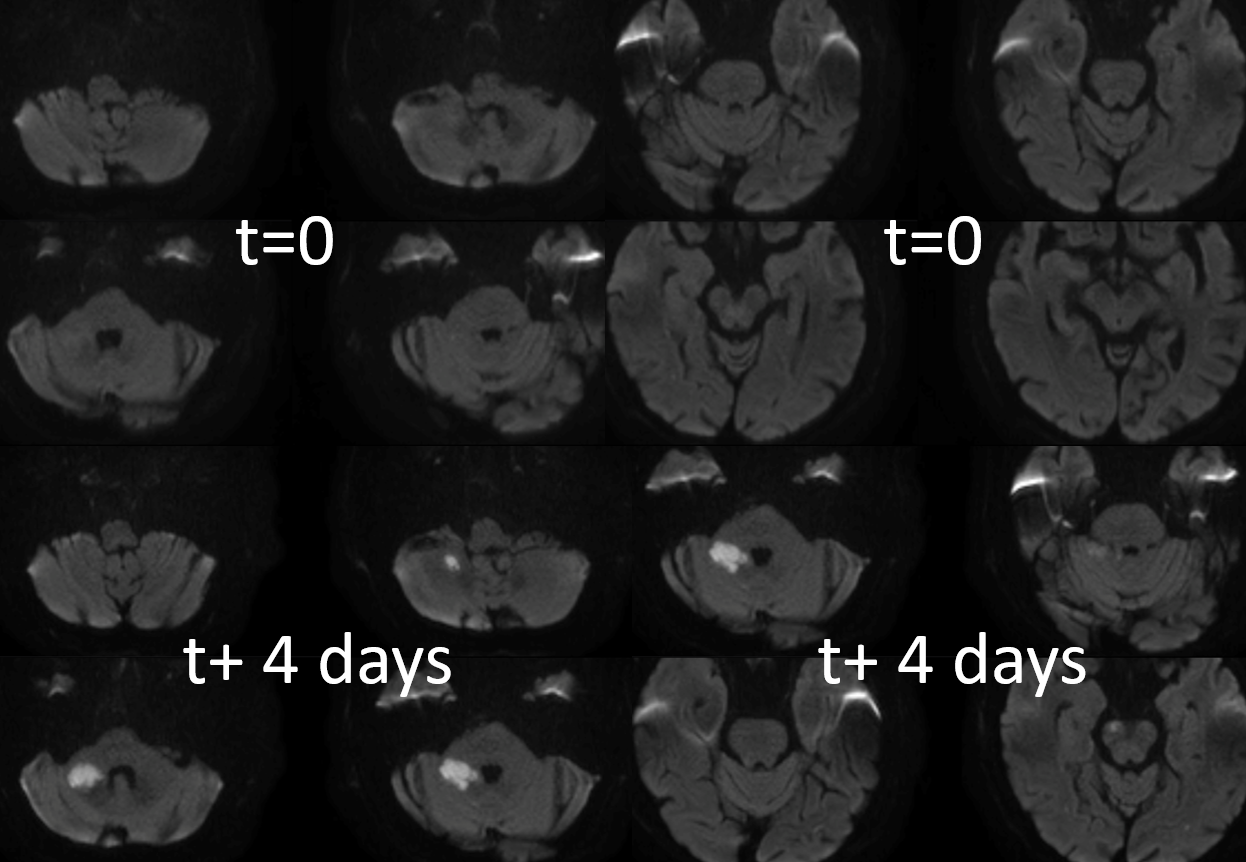

Back with a vengeance

At first wire goes into subintimal channel — see how it stays on the side and does not advance in the movie below?

Now the good way

Once you are through, follow the wire with microcatheter, replace wire with snare, catch the wire coming up from below, and bring it up through the stenosis… sounds easy, huh…

Now, image through a microcatheter from below